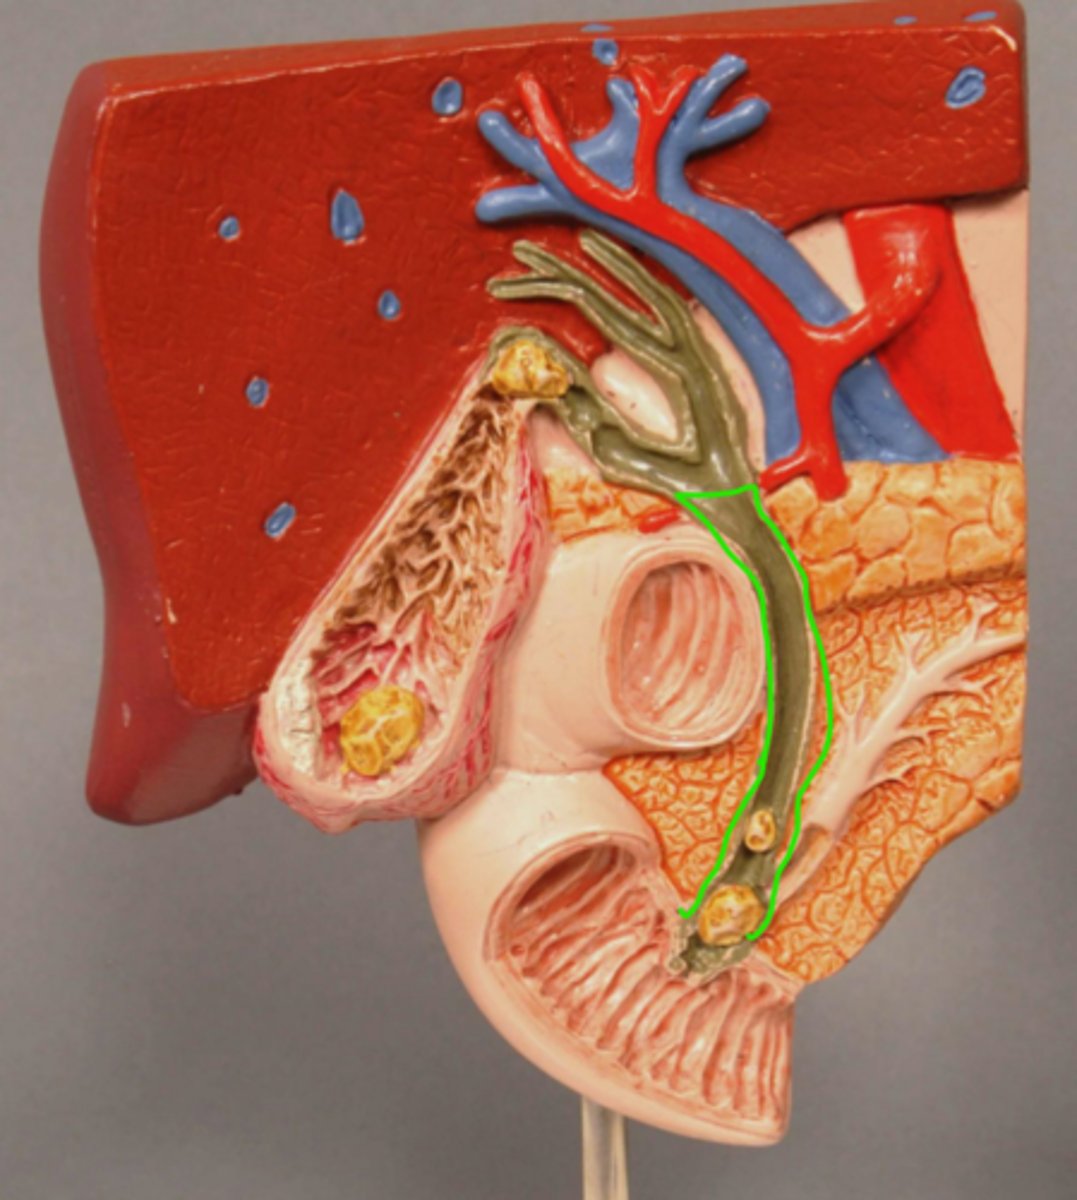

Common Bile Duct

Sphincter of Oddi

Pancreatic Duct

Gallstone in Bile Duct

Gallstone in Ampulla of Vater